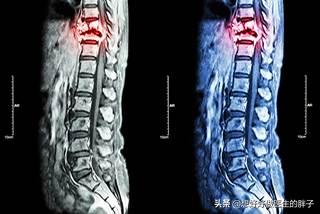

骨転移の磁気共鳴画像法

胸椎に発生した骨転移性癌を示す。